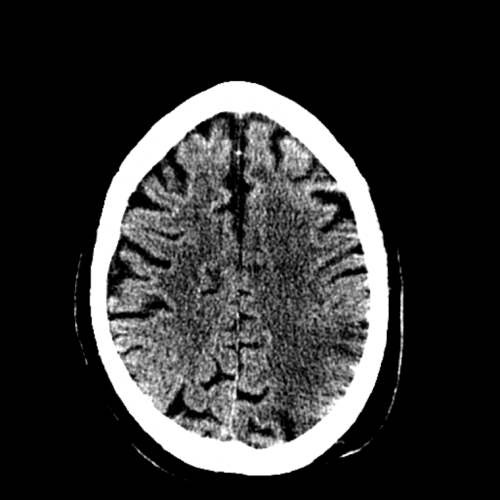

- Insular ribbon sign